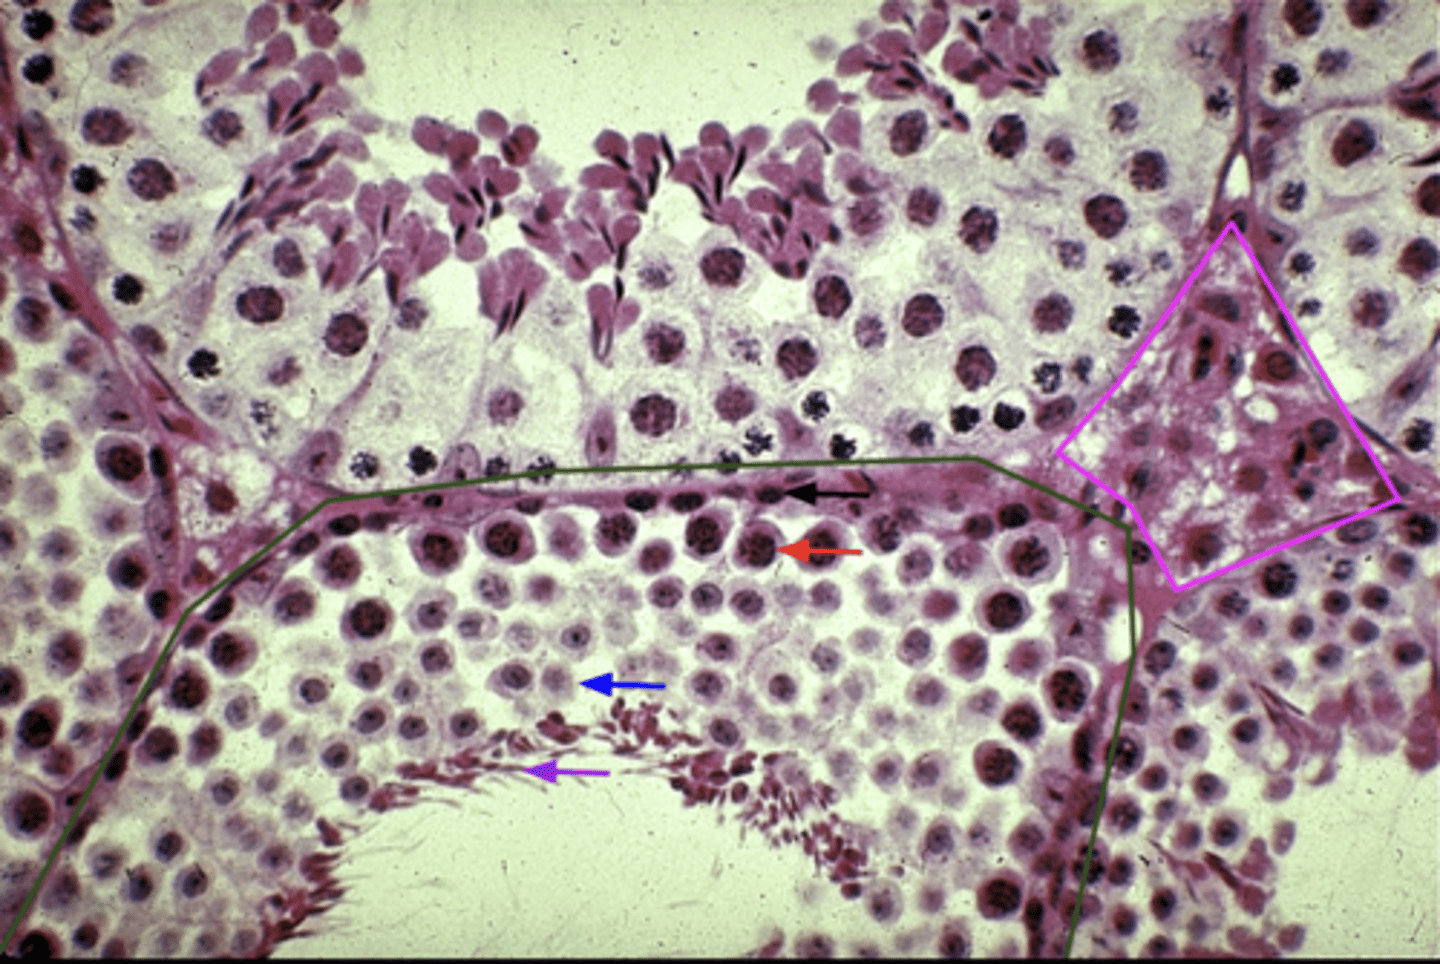

What is the green outline?

Spermatogonium

What is the black arrow?

Primary spermatocyte

What is the red arrow?

Spermatid

What is the blue arrow?

Spermatozoon

What is the purple arrow?

Interstitial cells

What is the pink outline?

Site of sperm production

Function of the seminiferous tubule?

This is the outer layer and first part of spermatogenesis

1 spermatogonium makes ___ spermatids

Production of testosterone

Function of the interstitial cells?

In examining an image of the seminiferous tubule, you notice a cell that lacks a flagellum and is not part of either two outermost layers what could this be and why.